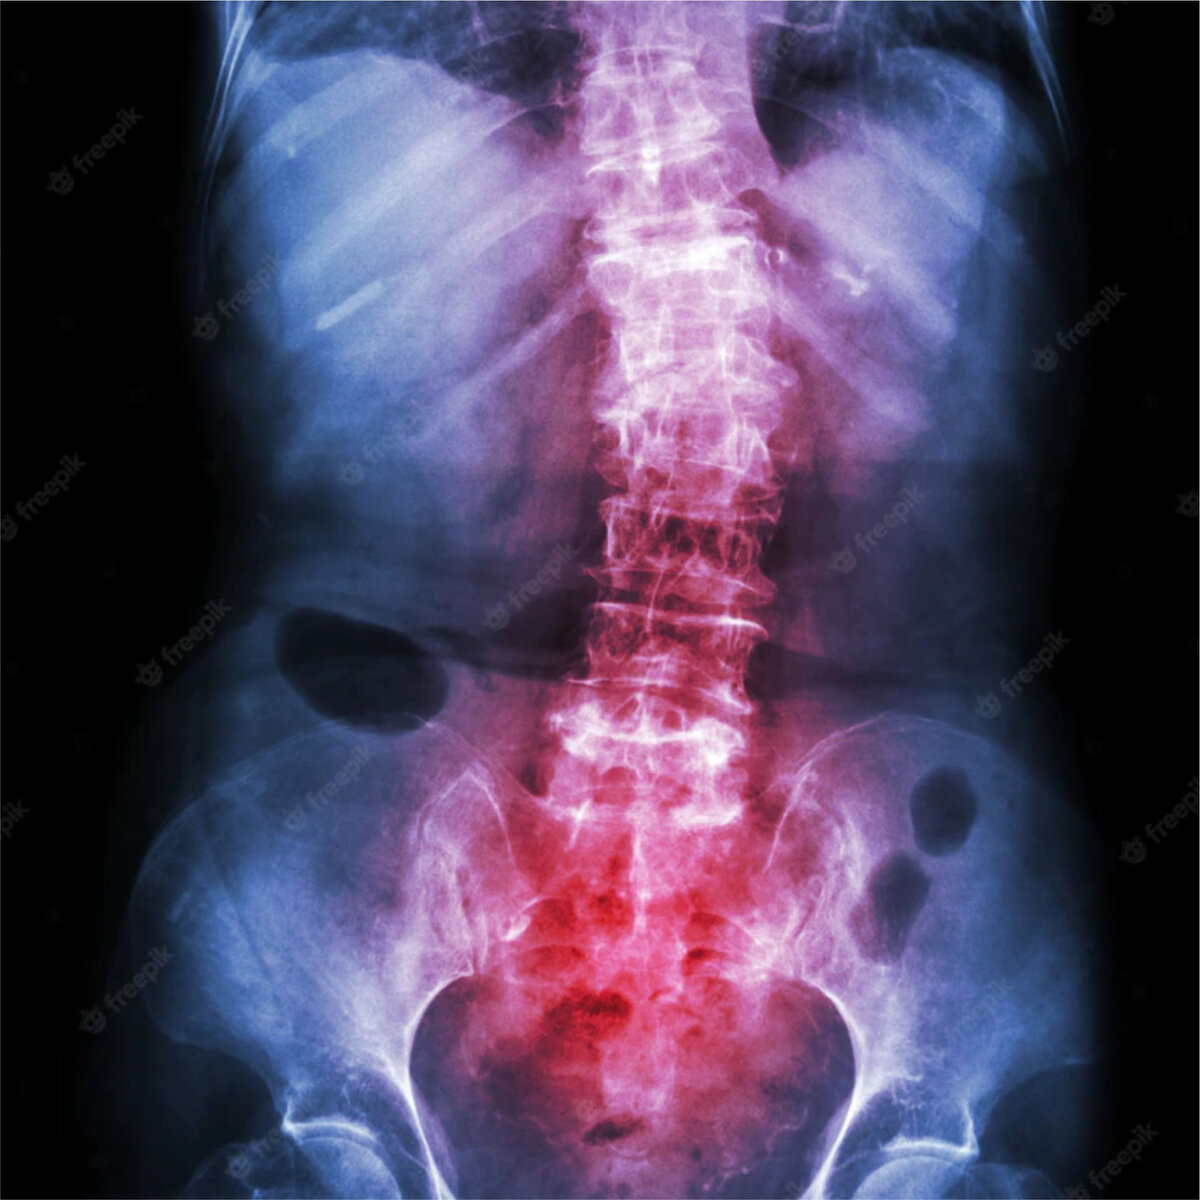

В описаниях МРТ исследований, в особенности пояснично-крестцового отдела позвоночника, очень часто встречается термин Спондилоартроз. Разберемся в этом понятии. Позвоночник представляет собой сложную структуру, которую анатомически можно разделить на две части. Передняя состоит из цилиндрических тел позвонков, соединенных друг с другом межпозвонковыми дисками и удерживающими их связками. Задняя часть представляет собой дужки позвонков, которые сочленены со смежными позвонками дугоотростчатыми, или фасеточными суставами. Источником боли в спине могут быть различные структуры, включая межпозвонковые суставы – дугоотростчатые сочленения. Спондилоартроз, или фасеточный синдром представляет собой заболевание, характеризующееся дегенеративными и дистрофическими изменениями фасеточных суставов позвоночника. Нередко оно может являться следствием остеохондроза, как компенсация. Изменения начинаются с суставного хряща – он истончается, становится неэластичным, в связи с чем не может в полной мер

Спондилоартроз, или фасеточный синдром представляет собой заболевание, характеризующееся дегенеративными и дистрофическими изменениями фасеточных суставов позвоночника. Нередко оно может являться следствием остеохондроза, как компенсация.

Изменения начинаются с суставного хряща – он истончается, становится неэластичным, в связи с чем не может в полной мере осуществлять свои функции. Процесс разрушения хрящевой ткани может затронуть и околосуставные участки костей. Со временем на них появляются наросты, которые приносят пациенту ощутимый дискомфорт во время двигательной активности.